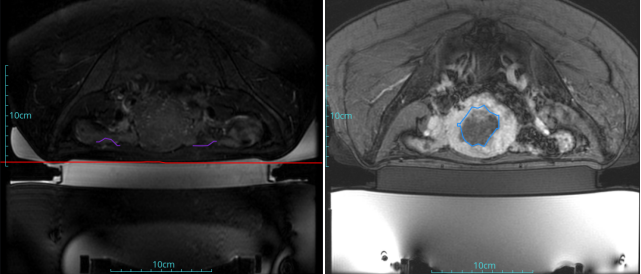

進一步了解收起

子宮肌瘤

患者信息:女,38

診斷:子宮肌瘤

腫瘤尺寸:約為38*40*42mm

ROT深度:腫瘤的ROT中心距離皮膚62mm

術后評估:術后造影增強圖像顯示消融區(qū)域(右側)與腫瘤區(qū)域(左側)重合度較好,且非灌注區(qū)域連續(xù)且一致。

結論:對該腫瘤具有非常好的消融效果,治療過程中,溫度上升曲線符合預期,每個被治療的靶點240CEM區(qū)域體積較大、外形飽滿、連續(xù)。病灶消融良好,NPV體積比約87.88%。